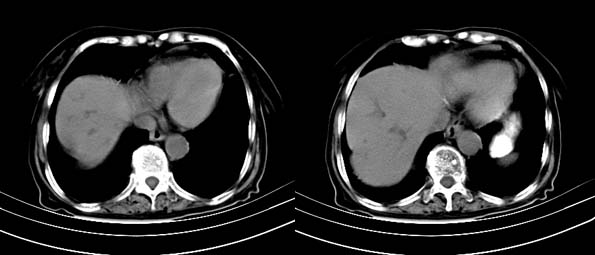

以下是引用bailaode在2008-6-12 22:10:00的发言:[br]资料中未提及患者有无急腹症体征,这个很重要。[br] ct表现:肝内境界模糊之低密度灶,内有含对比剂之液气平面.(提示肝内病灶与胃肠道沟通) [br] 1、根据“长城干红 ”所提供的资料“患者,女,74岁,黑便月余,消瘦,一般状况差,白细胞1万四千”,是否可认为是个慢性病程?那么我首先考虑:十二指肠结核,十二指肠--胆管瘘,继发胆道逆行感染肝脓肿形成。[br] 2、如有急腹症体征则考虑:十二指肠溃疡穿孔?十二指肠占位伴穿孔?

以下是引用拾荒者在2008-6-13 22:13:00的发言:[br]病灶与升结肠、肝脏及十二指肠关系密切,且结肠降段见造影剂影,支持结肠与十二指肠瘘形成,原因及原发病在哪不好定,不过,虽说有风险,但还是应该手术治疗,单纯抗感染估计不行。